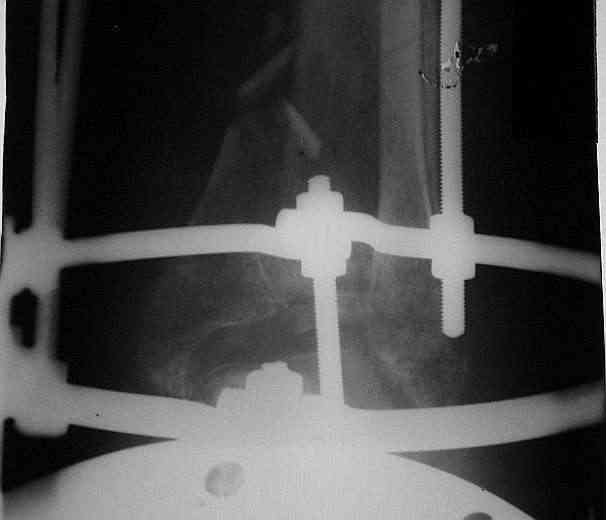

Было решено, уже по ходу операции, выполнить артродез болтом-стяжкой, тем самым компрессируя резецированные суставные поверхности и смещая стопу латерально, дабы нивелировать варусную деформацию и восстанавливая тем самым опорную ось всей конечности.

Вчера (прошло около 8 месяцев)больной обратился ко мне в очередной раз с жалобами на боли умеренно-жгучего характера в области выстояния концов болта-стяжки. На момент осмотра:укорочение левой нижней конечности на 1,5 см; гипотрофия медиальной группы мышц голени и четырехглавой мышцы бедра; передвигается без дополнительной опоры в ортопедической обуви на растояние до 5 км; работает приемщиком цветных металлов (приходится перетаскивать грузы). Нарентгенограмме, насколько это можно видеть, костного блока сформировать не удалось, но движений в голеностопном суставе нет - ни активных, ни пассивных. Послеоперационные рубцы б/о; свищей и нагноения не было. Активно больногонаблюдать не приходилось, т.к. проживает в другом городе.

Стоит ли необходимость удаления болта-стяжки из-за болевого синдрома?

ЗЫ: Прошу прощения за очень низкое качество представленных ренгенограмм. Буду очень признателен за комментарии.